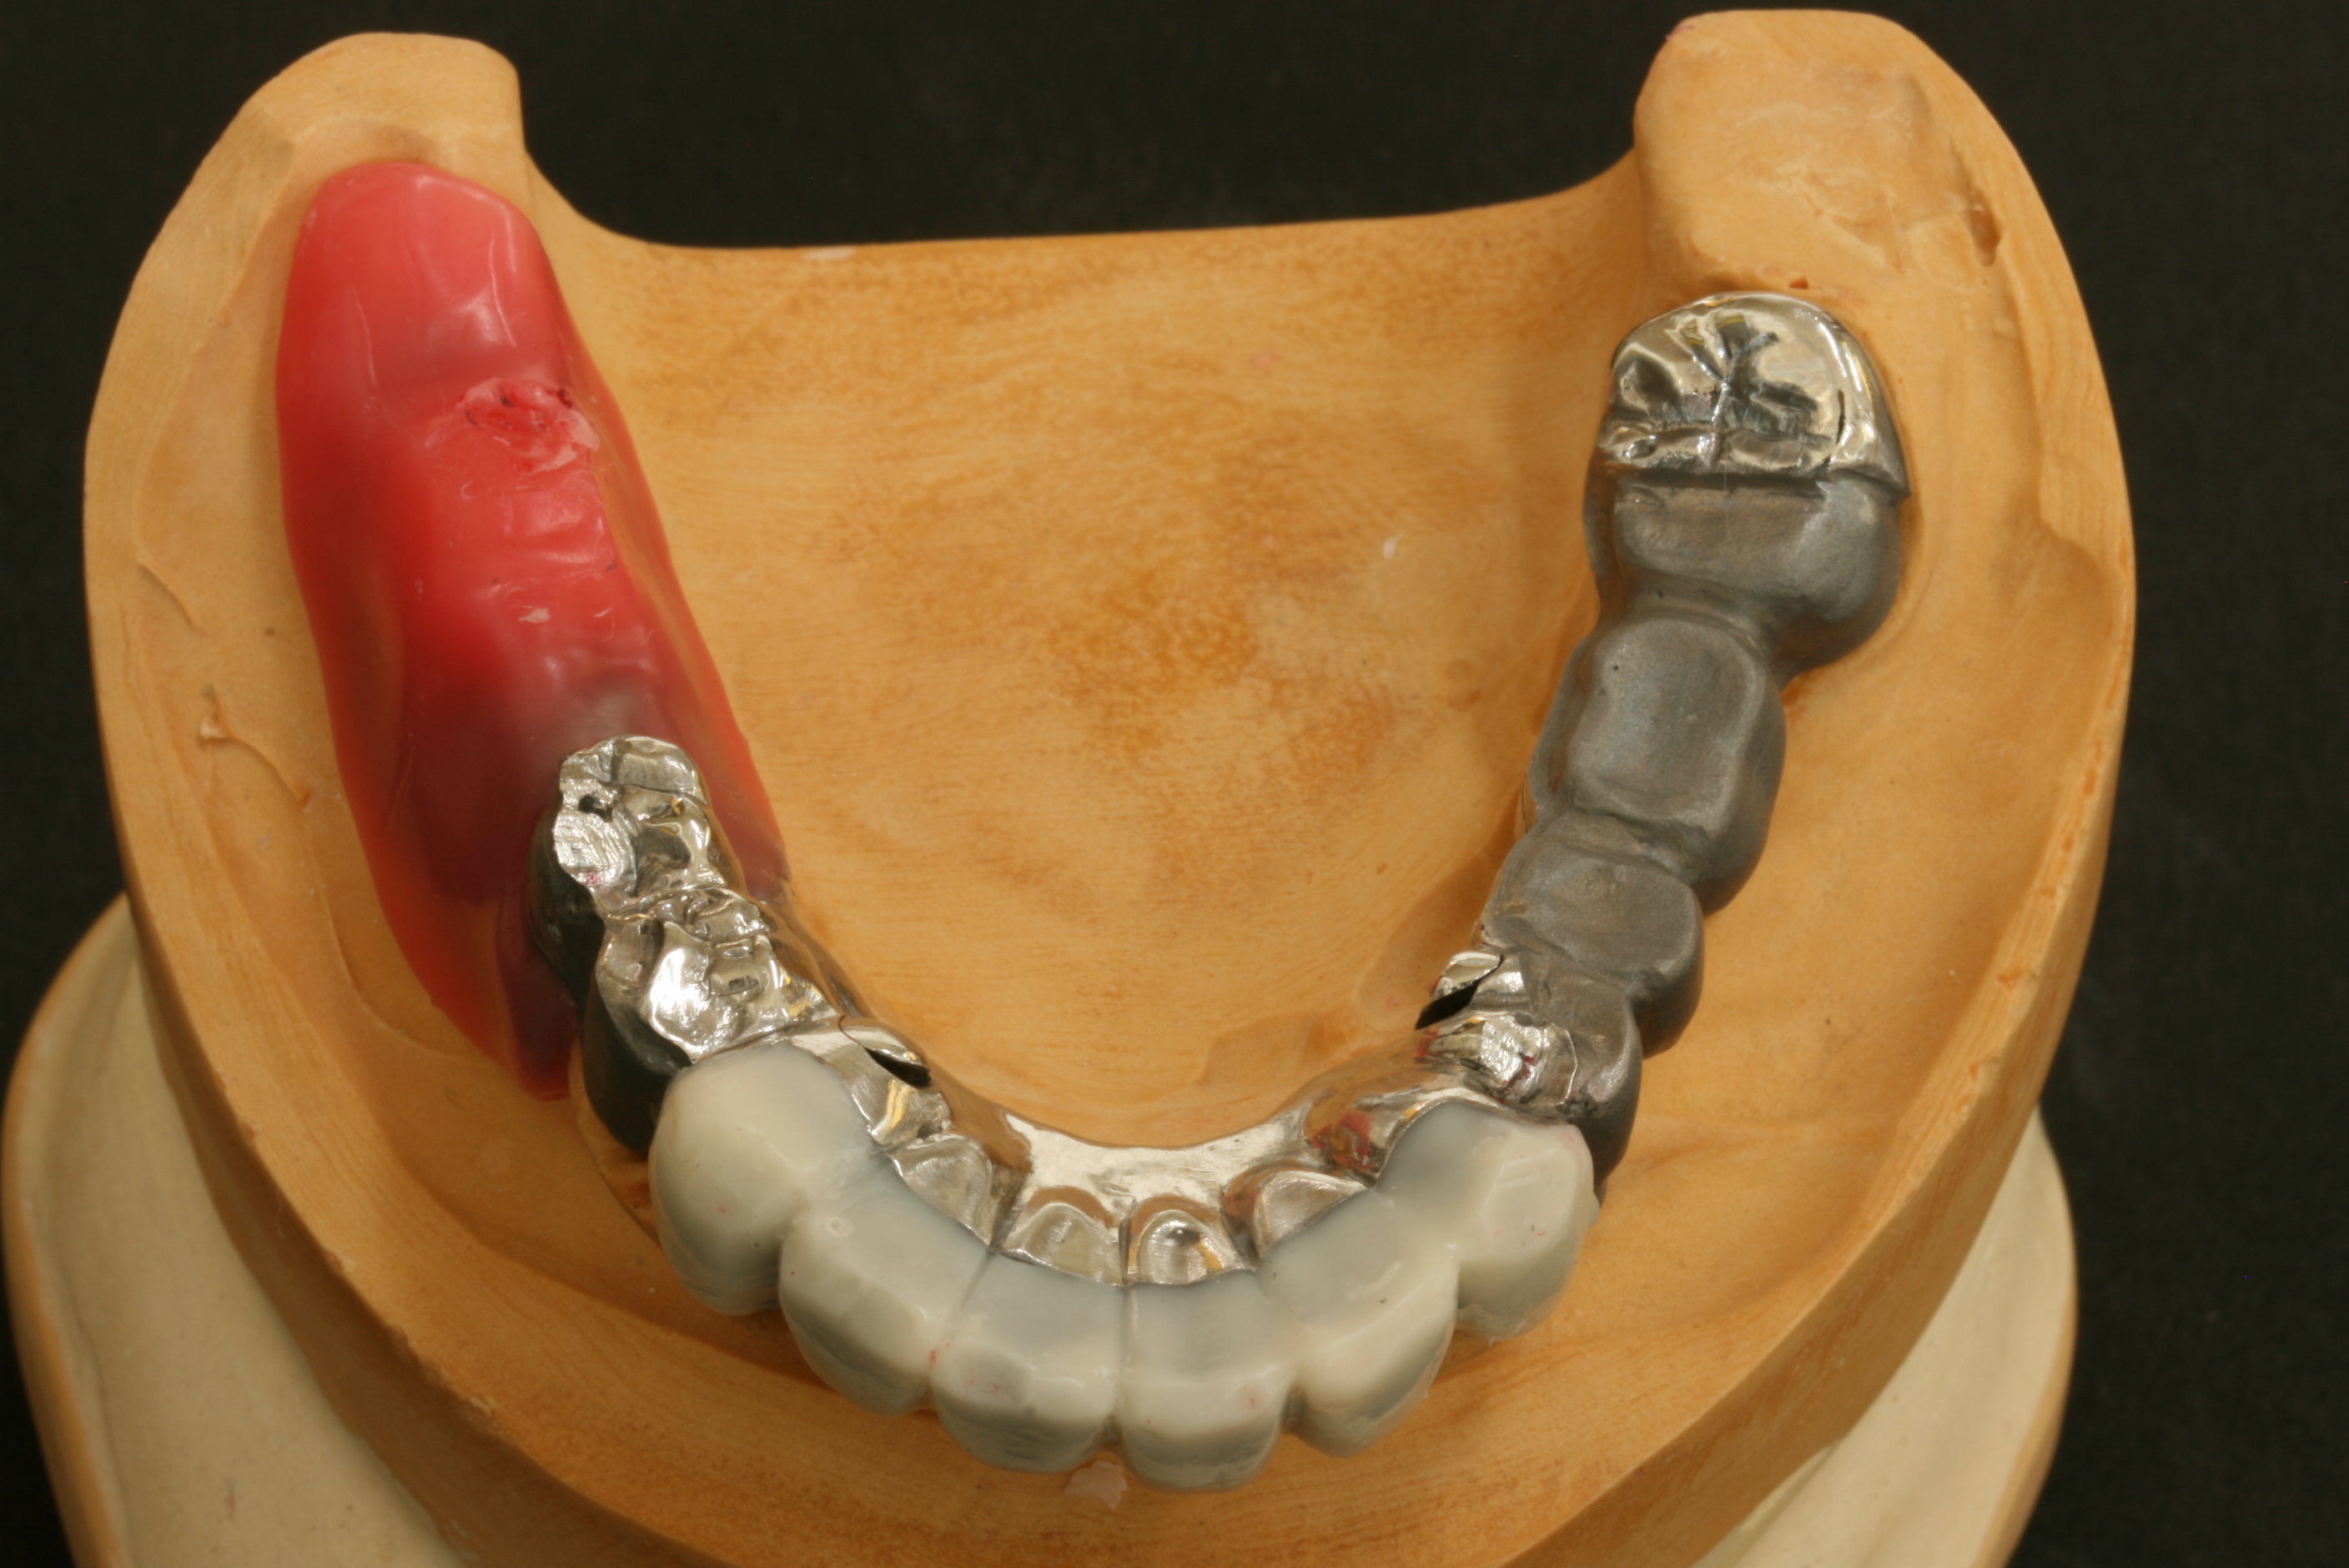

まず、内冠を患者さんの歯に仮止めしてから、その上に外冠を合わせて、噛み合わせを見ます。

前歯の白い部分は仕上がりをイメージして、ワックスで仮に仕上げてあります。

この入れ歯は、奥歯のほとんどの部分を白く仕上げる予定です。

白い部分は、陶材(ポーセレン)を焼き付けて美しく仕上げる予定です。

テレスコープにおいては、技術的に非常に難しい仕上げ方ですが、順調に試適を終えました。